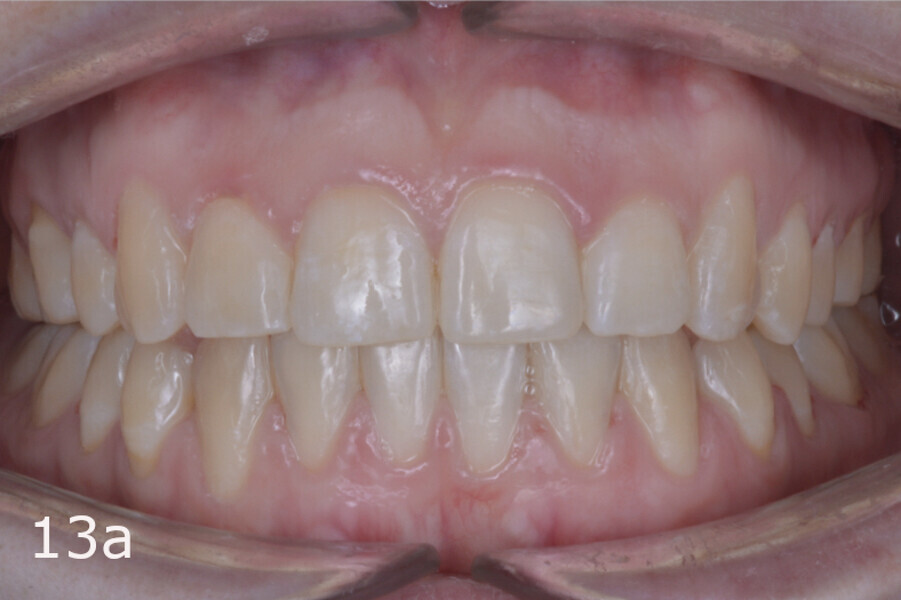

The total treatment time was 15 months. An Angle Class I relationship was established along with adequate anterior and canine guidance, establishing a functional occlusion. This not only ensures optimal masticatory function but also protects the teeth and the temporomandibular joint from excessive force. Maxillary and mandibular fixed retention were installed at the end of the treatment (Figs. 13–19).